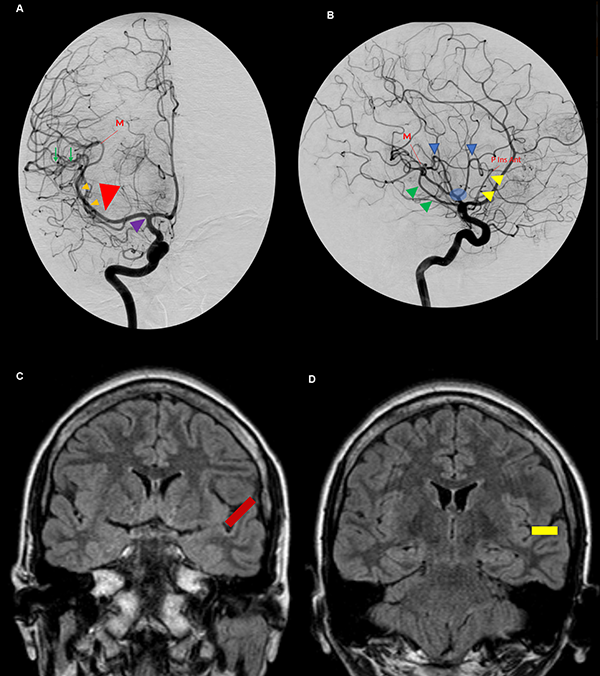

Figura 11: A. Vista anteroposterior de una angiografía carotídea derecha. El uncus (cabeza de flecha violeta) se relaciona anteriormente con el segmento proximal de M1. El ápex uncal apunta hacia la bifurcación carotídea. Inmediatamente distal al genu de la ACM se ubica la pars triangularis (cabeza de flecha roja grande). Las pequeñas cabezas de flecha naranjas indican el segmento M2 de la ACM y, consecuentemente, la corteza insular. El punto M se define como el punto donde el ramo más posterior de M2 cambia de sentido alejándose de la ínsula hacia el opérculo, en relación estrecha con el extremo posteromedial del giro de Heschl. La ínsula se proyecta desde el genu de la ACM hasta el punto M. Las ramas de M3 sobre el plano temporal tienen un curso recto (flechas verdes). B. Vista lateral de la misma angiografía. Se identifica el triángulo silviano. Su borde anterior (cabeza de flecha amarillo) y superior (cabezas de flecha azul) lo marcan los loops de M2. Su borde inferior lo indica el tronco inferior de M2 cursando por el surco limitante inferior insular (cabeza de flecha verde). Los troncos postbifurcación se ramifican cerca del polo insular y el ápex (círculo celeste). C y D. Vistas coronales de una RMN. El plano polar tiene una dirección oblicua inferior (barra roja) (C) y el plano temporal una dirección recta (barra amarilla) (D). P Ins Ant: punto insular anterior.

Se dice que la angiografía digital (AD) muestra el esqueleto en el cual las estructuras neurales son organizadas. Su comprensión profunda es esencial para el planeamiento quirúrgico. La corteza insular está cubierta e irrigada por el segmento M2 (Figura 7A). Consecuentemente, en una AD, el lóbulo insular se localiza inmediatamente medial a M2 (Figura 11A y B).21 Los límites anterior, superior e inferior del lóbulo insular también pueden ser reconocidos en la AD. Los puntos de cambio de dirección, o loops, de la ACM distal al genu marcan la transición M2/M3 y se localizan en el surco limitante insular anterior y superior (Figura 7A y B). El tronco inferior de M2 cursa a lo largo del surco limitante inferior (Figura 7A). El punto donde el ramo más posterior de M2 cambia de dirección y se aleja de la ínsula dirigiéndose hacia el opérculo temporal (transición M2/M3) es el punto M o silviano, en la AD (Figura 12B, 11A, 11B).12,14,15,26,30 El punto M es un reparo imagenológico de gran utilidad. Este punto indica el extremo posterior insular y la parte más posteromedial del giro de Heschl. Así también, en una incidencia anteroposterior, el punto M indica la posición de, de lateral a medial, el brazo posterior de la cápsula interna, el pulvinar del tálamo y el atrio (Figura 12B).

El triángulo silviano6,14,15 es un reparo encontrado en la incidencia lateral estricta en un AD. Sus bordes son dibujados por los loops M2 anterior y superiormente, y por el tronco inferior cursando por el surco limitante inferior insular, inferiormente. Este triángulo tiene un ángulo superoanterior recto, marcando el punto insular anterior. El contenido de este triángulo es el lóbulo insular y el core central. Inmediatamente por fuera del triángulo se encuentran los ventrículos laterales (Figura 11B).

La bifurcación carotídea se relaciona con el ápex uncal y el segmento proximal de M1 se relaciona inferiormente con el segmento anterior del uncus. Más aún, el genu de M1 se localiza en el limen insular, por lo tanto, en una AD, marca el borde anterior de la ínsula. La pars triangularis está ubicada unos milímetros distales al genu de M1. Dado que el giro precentral cubre el tercio medio de la ínsula, se puede inferir que el giro precentral en una AD se localiza en el punto medio del triángulo silviano. Finalmente, el extremo posterior del lóbulo insular se localiza en el punto M. Consecuentemente, lesiones vascularizadas localizadas en el genu de M1, son encontradas unos pocos milímetros proximales a la pars triangularis, cerca del polo insular; lesiones localizadas inmediatamente distal al genu, se relacionan superficialmente con la punta de la pars triangularis; y aquellas posicionadas en el punto medio entre el genu y el punto M, son mediales al giro precentral (Figura 11A y B).15

Las ramas M3 que cursan sobre el plano polar son más curvilíneas que aquellas del plano temporal, a causa de la superficie relativamente más plana de la primera. El primer segmento recto de M3 identifica el extremo lateral del giro de Heschl (Figura 11A).15 Entonces, el giro de Heschl está enmarcado entre el punto M y el primer tramo recto de M3 (Figura 7B).